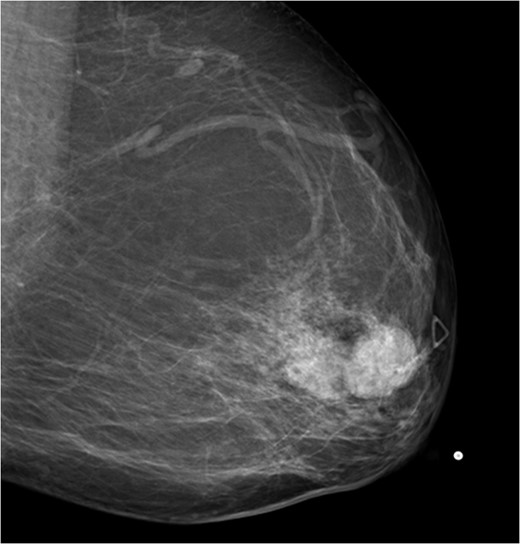

A 56-year-old black female presented to the surgical clinic with a palpable left breast mass that had grown over several months. She denied nipple discharge, breast retraction or family history of malignancy. Physical exam revealed a palpable, subareolar mass without skin changes or asymmetry, and no lymphadenopathy. Her mammogram revealed a 5.4 × 3 cm lesion behind the nipple with Breast Imaging-Reporting and Data System (BI-RADS) 5 classification. An ultrasound indicated a 2.2 × 2 cm lobulated hypoechoic mass with BI-RADS 4 classification (Figs 1–3).

Mammogram mediolateral view of left breast showing lesion posterior to nipple BI-RADS 5.